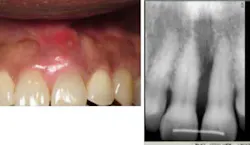

Case No. 3 — Mr. First Time

A 79-year-old African American male was diagnosed with chronic periodontitis. He had no prior dental care and presented with full dentition, no caries, and advanced bone loss with tooth mobility in molar areas. His chief complaint was a loose upper right tooth. The LANAP protocol was performed over two appointments with local anesthetic. Treatment was done in August 2012.

Mr. First Time before the LANAP protocol.

Mr. First Time is very pleased with his care despite his initial trepidation. Tooth mobility has lessened, and sensitivity is minimal despite the significant amount of calculus removal that was done and the resulting root exposure. The tooth with +3 mobility was removed. The patient realizes other teeth may need extraction, but at this time no additional extractions are planned. (November 2012)

Mr. First Time after treatment.